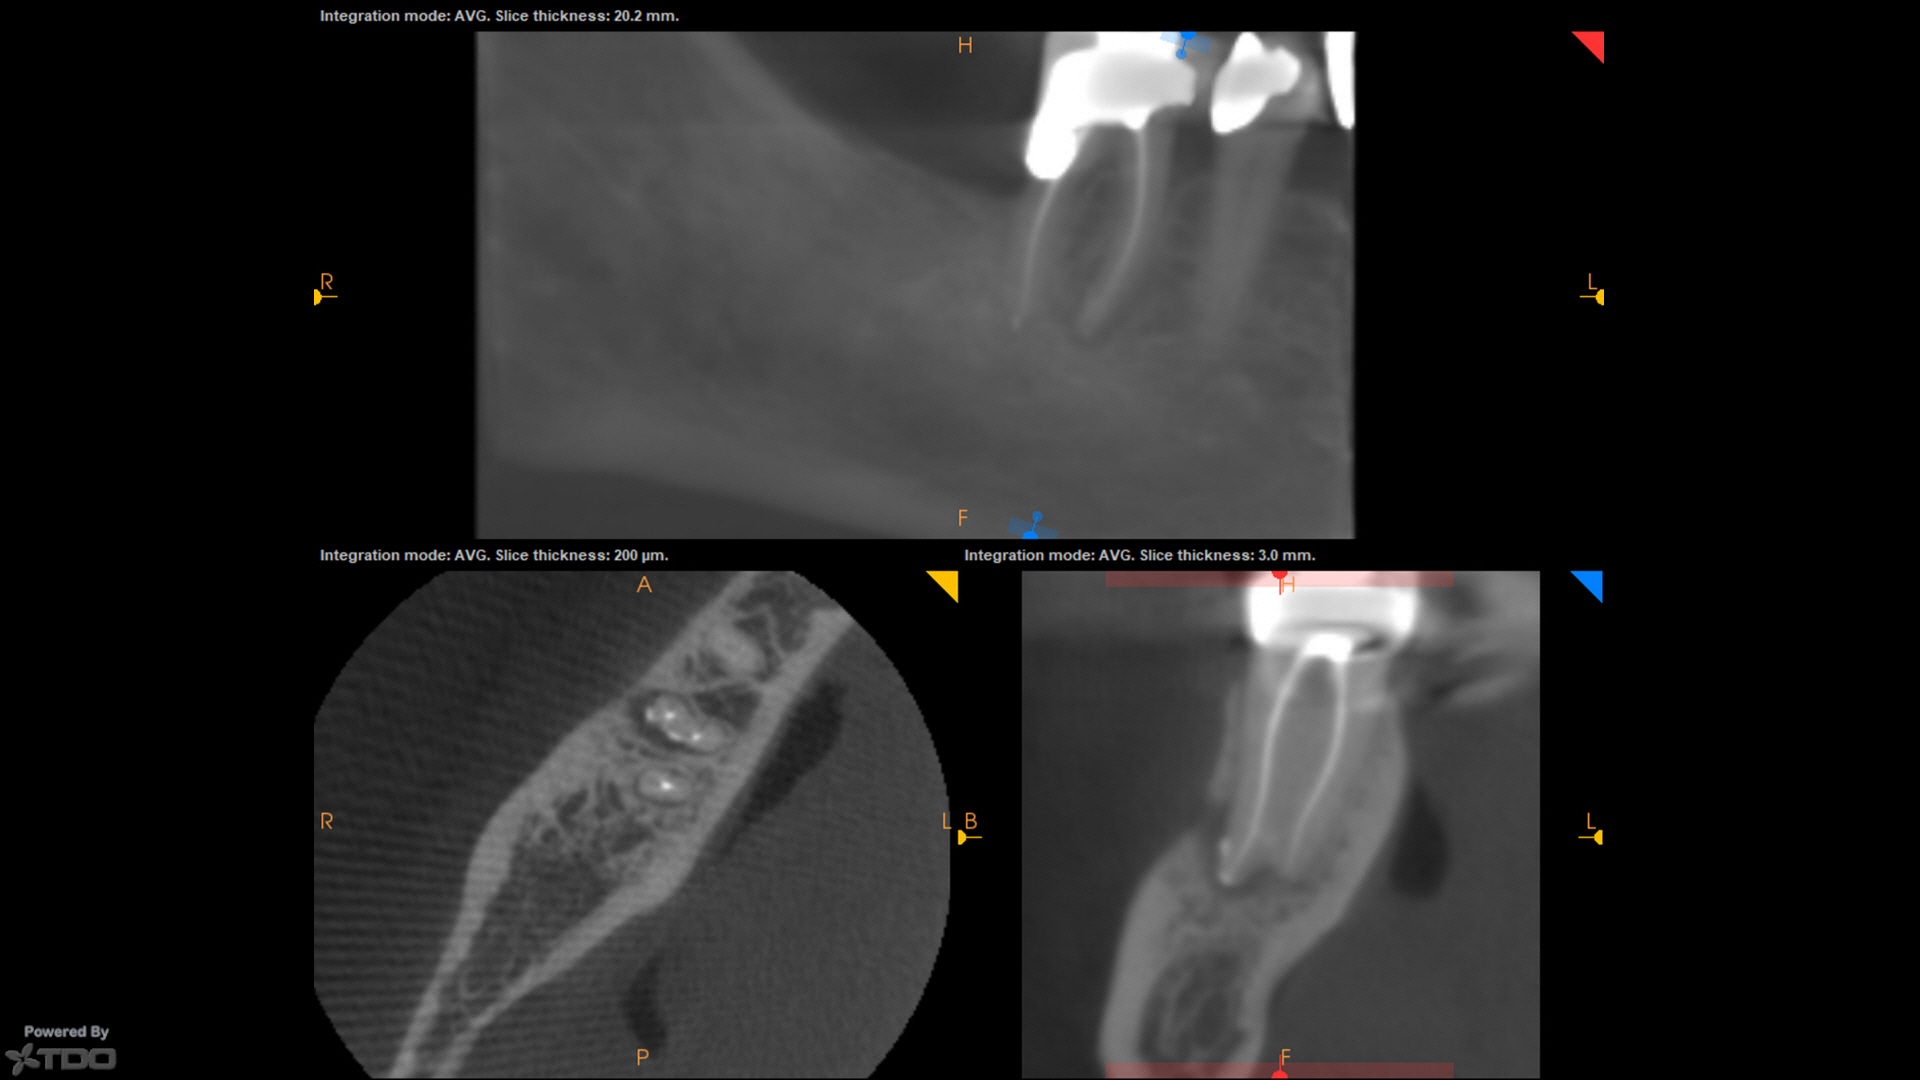

CBCT post-op on the one from today demonstrating some apical anatomy if that tickles your fancy.